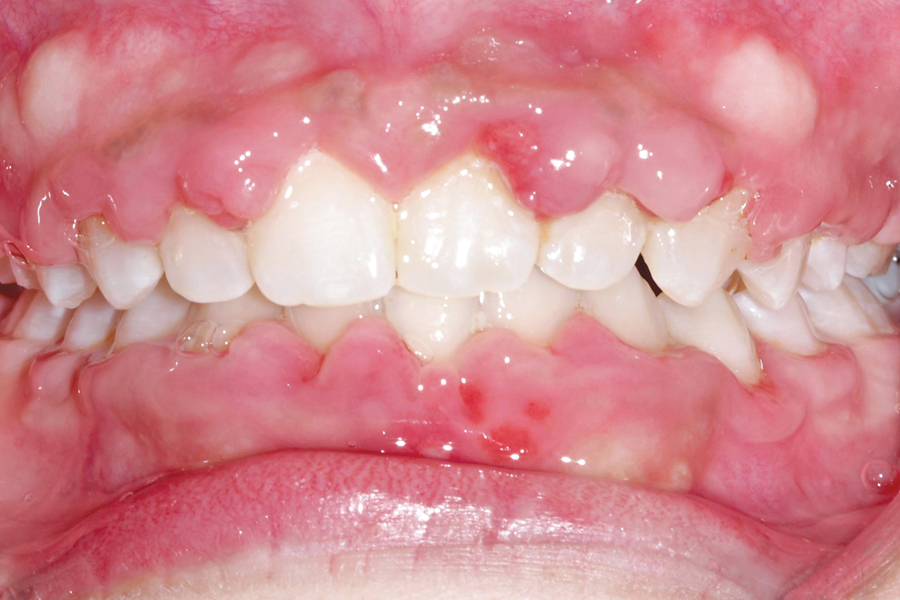

Figure B. After orthodontic treatment. Note hyperplasia of gingival secondary to anti-seizure medication

One of the foundations upon which health care professionals practice is a commitment to provide the best possible treatment to each and every one of their patients. For some patients, medical or socioeconomic circumstances may present a challenge to the delivery of optimal care. Fortunately, we live and practice in a country that provides an … Read more